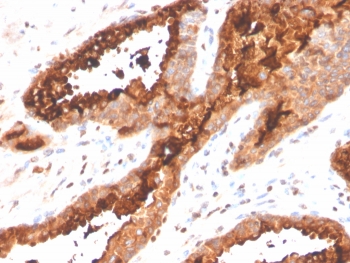

Prostatic acid phosphatase Antibody immunohistochemistry analysis of PAP / ACP3 in human prostate carcinoma tissue. FFPE human prostate carcinoma tissue was stained with Prostatic acid phosphatase Antibody (recombinant rabbit monoclonal, clone ACPP/4495R) following heat induced epitope retrieval by boiling tissue sections in pH 9 Tris-EDTA buffer (10mM Tris, 1mM EDTA) for 20 minutes prior to cooling and staining. HRP-DAB brown chromogenic signal highlights strong cytoplasmic and membranous staining of prostate tumor epithelial cells forming glandular carcinoma structures, consistent with the known localization of Prostatic acid phosphatase (ACP3 / PAP) in prostate-derived epithelial cells. Detection of PAP expression by immunohistochemistry is widely used in prostate cancer research to identify prostate epithelial lineage and evaluate Prostatic acid phosphatase expression in prostate carcinoma tissues.

IHC staining of FFPE human prostate carcinoma tissue with Prostatic acid phosphatase antibody (clone ACPP/4495R). HIER: boil tissue sections in pH 9 10mM Tris with 1mM EDTA for 20 min and allow to cool before testing.